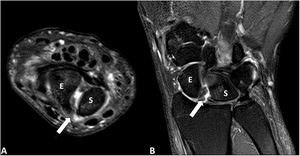

Resonancia magnética. Imágenes axial (A) y coronal (B) de la muñeca izquierda en secuencias potenciadas en T2 con supresión grasa (SPAIR). Se objetiva una rotura completa de la porción dorsal del ligamento escafosemilunar (flecha) que produce una diástasis significativa entre el hueso escafoides (E) y el semilunar (S) con mínima cantidad de derrame y signos de sinovitis. No se objetivan focos de señal de resonancia similar a edema óseo que sugieran inflamación/artritis ni cambios artrósicos significativos.